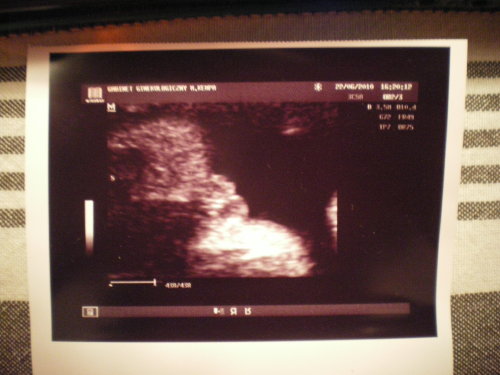

Zdjęcia USG Naszych dzieciątek :)))

Pipusia pośrodku i dwa półdupki po bokach:-D moje przesłodkie maleństwo..:)